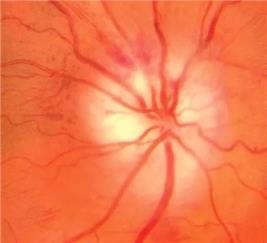

颞动脉炎导致缺血性视神经病变颞动脉炎(GCA),又称巨细胞动脉炎,是一种慢性系统性血管肉芽肿性炎症,病因尚不清楚。主要累及中动脉及大动脉,包括主动脉及其分支、颈外动脉,累及供应眼动脉及其分支时可导致失明。

GCA 导致的前部缺血性视神经病变表现为无痛、非进行性的视力严重减退,眼底检查可见视乳头局限水肿、周围线状出血。早期诊断和及时的激素冲击对拯救视力极其重要。